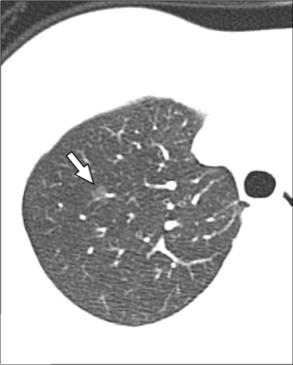

CT主要表现为三处非常细小的渗出(图1-3箭头所示):

图1

回到这个小护士病例,根据水痘表现,加上影像学表现为GGO、小结节周围GGO,应该比较符合的,可以临床诊断为水痘肺炎。但本病例仅发现3个小病灶,没有广泛累及,推测原因可能是先前可能接种过水痘疫苗,肺部累及较轻。

本例患者是因筛查新冠CT检查而意外发现的轻微的水痘肺炎,病程中并无明显咳嗽、气急与呼吸困难。当然此例水痘肺炎是建立在临床诊断基础之上,有必要进一步跟踪随访。